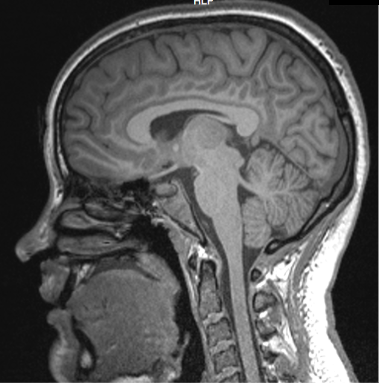

Jenessa's Brain:

<figcaption>Jenessa's brain sMRI</figcaption> </figure> Are you an expert in something and want to be on the show? Apply here!